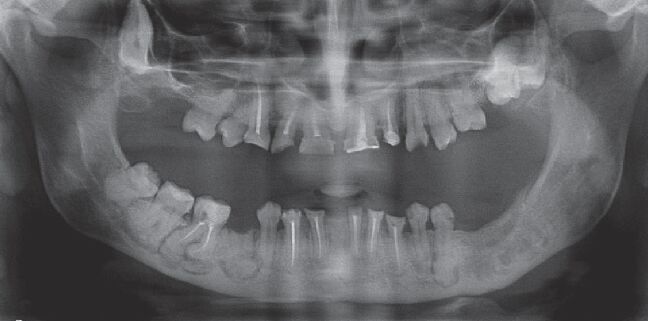

66.17歲男孩因上顎右側有一個無疼痛的腫脹而來求診,經X光檢查(如附圖)發現一個放射線不透過性影像如 箭頭所示之區域,根尖片可見到此病變與周圍界線不清楚,此病患最可能罹患下列何種疾病?

(A)家族性巨大畸形牙骨質瘤(familial gigantiform cementoma)

(B)繁盛性牙骨質骨發育不良(florid cemento-osseous dysplasia)

(C)纖維性發育不良(fibrous dysplasia)

(D)骨化纖維瘤(ossifying fibroma)

統計: A(127), B(94), C(780), D(137), E(0) #2625181